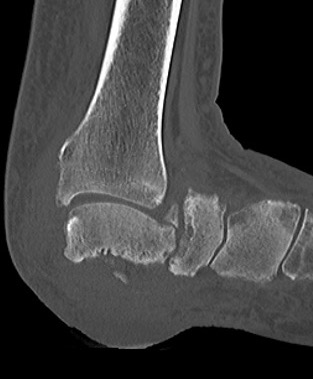

Xray

Midfoot collapse

Midfoot collapse and rocker bottom foot with small ulcer

Midfoot collapse with subluxation of midtarsal joints

Hindfoot collapse with ulcer